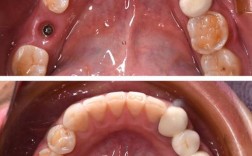

(图片来源网络,侵删)- 最看重什么? 是预算、速度、舒适度、美观度、咀嚼功能,还是长期效果?